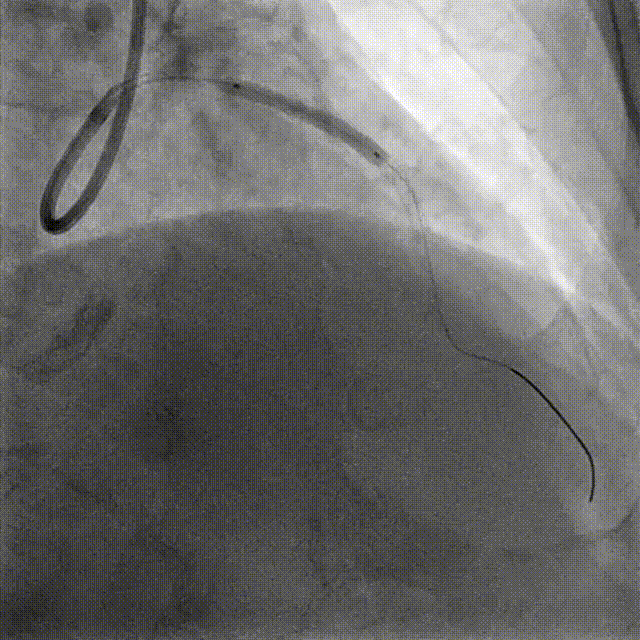

Lesion preparation NC 2.5*12mm → Cutting balloon 4.0*10mm @ 12atm

Angiography & DCB Angioplasty DCB 4.0*20mm @ 8atm, 60s